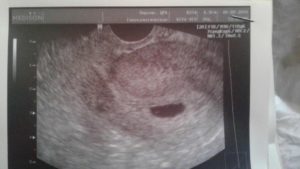

В этот же период начинается рост плаценты – уникального органа, обеспечивающего защиту и питание плода. Из трофобласта и эктодермы образуются амнион и хорион. Амниотическая полость заполняется околоплодными водами, а хорион начинает активно продуцировать ХГЧ. Размеры эмбриона достигают значения в 4 мм и его уже можно увидеть на УЗИ.

После проведения анализа на содержание в крови хорионического гонадотропина женщина уже может знать, что она носит в себе новую жизнь. Спустя 3 недели беременности, что происходит с плодом – можно разглядеть с помощью ультразвукового исследования.

На этом этапе эмбрион представляет собой крошечный шар с едва различимыми головным и хвостовым концами, окруженный плодным яйцом. УЗИ-диагностика на ранних сроках беременности проводится двумя способами:

Именно УЗИ на третьей неделе после введения эмбрионов является методом, позволяющим достоверно определить наличие беременности, так как ЭКО, к сожалению, не всегда может гарантировать удачный результат.

Кроме того с помощью ультразвукового сканирования можно увидеть:

• Количество жизнеспособных эмбрионов в матке;

• Место расположения плодного яйца;

• Изменения в яичниках.

Первое УЗИ является необычайно важным для исключения серьезных патологий в виде внематочной беременности, остановки развития плода, определения многоплодной беременности и необходимости дальнейшего проведения или коррекции поддерживающей терапии.